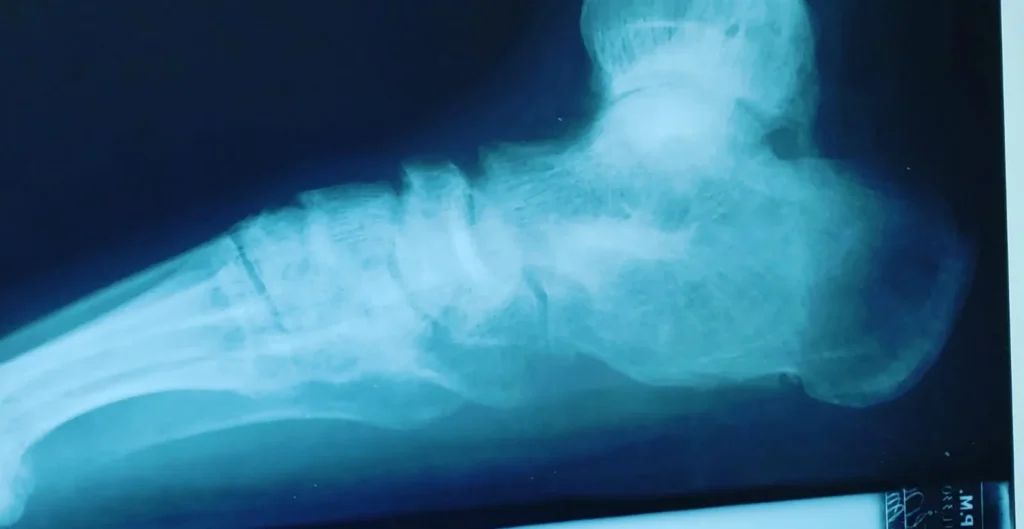

See What's Going on Inside Our Podiatrist's Office

With 32 years of experience, Dr. Daniel Brandwein DPM, PA, FACFAS is your trusted choice for podiatric care in the Pompano Beach, FL area. Take a look at the photos below to see what's happening inside our locally and family owned clinic. To find out how we can help with your foot care needs, please contact us today.